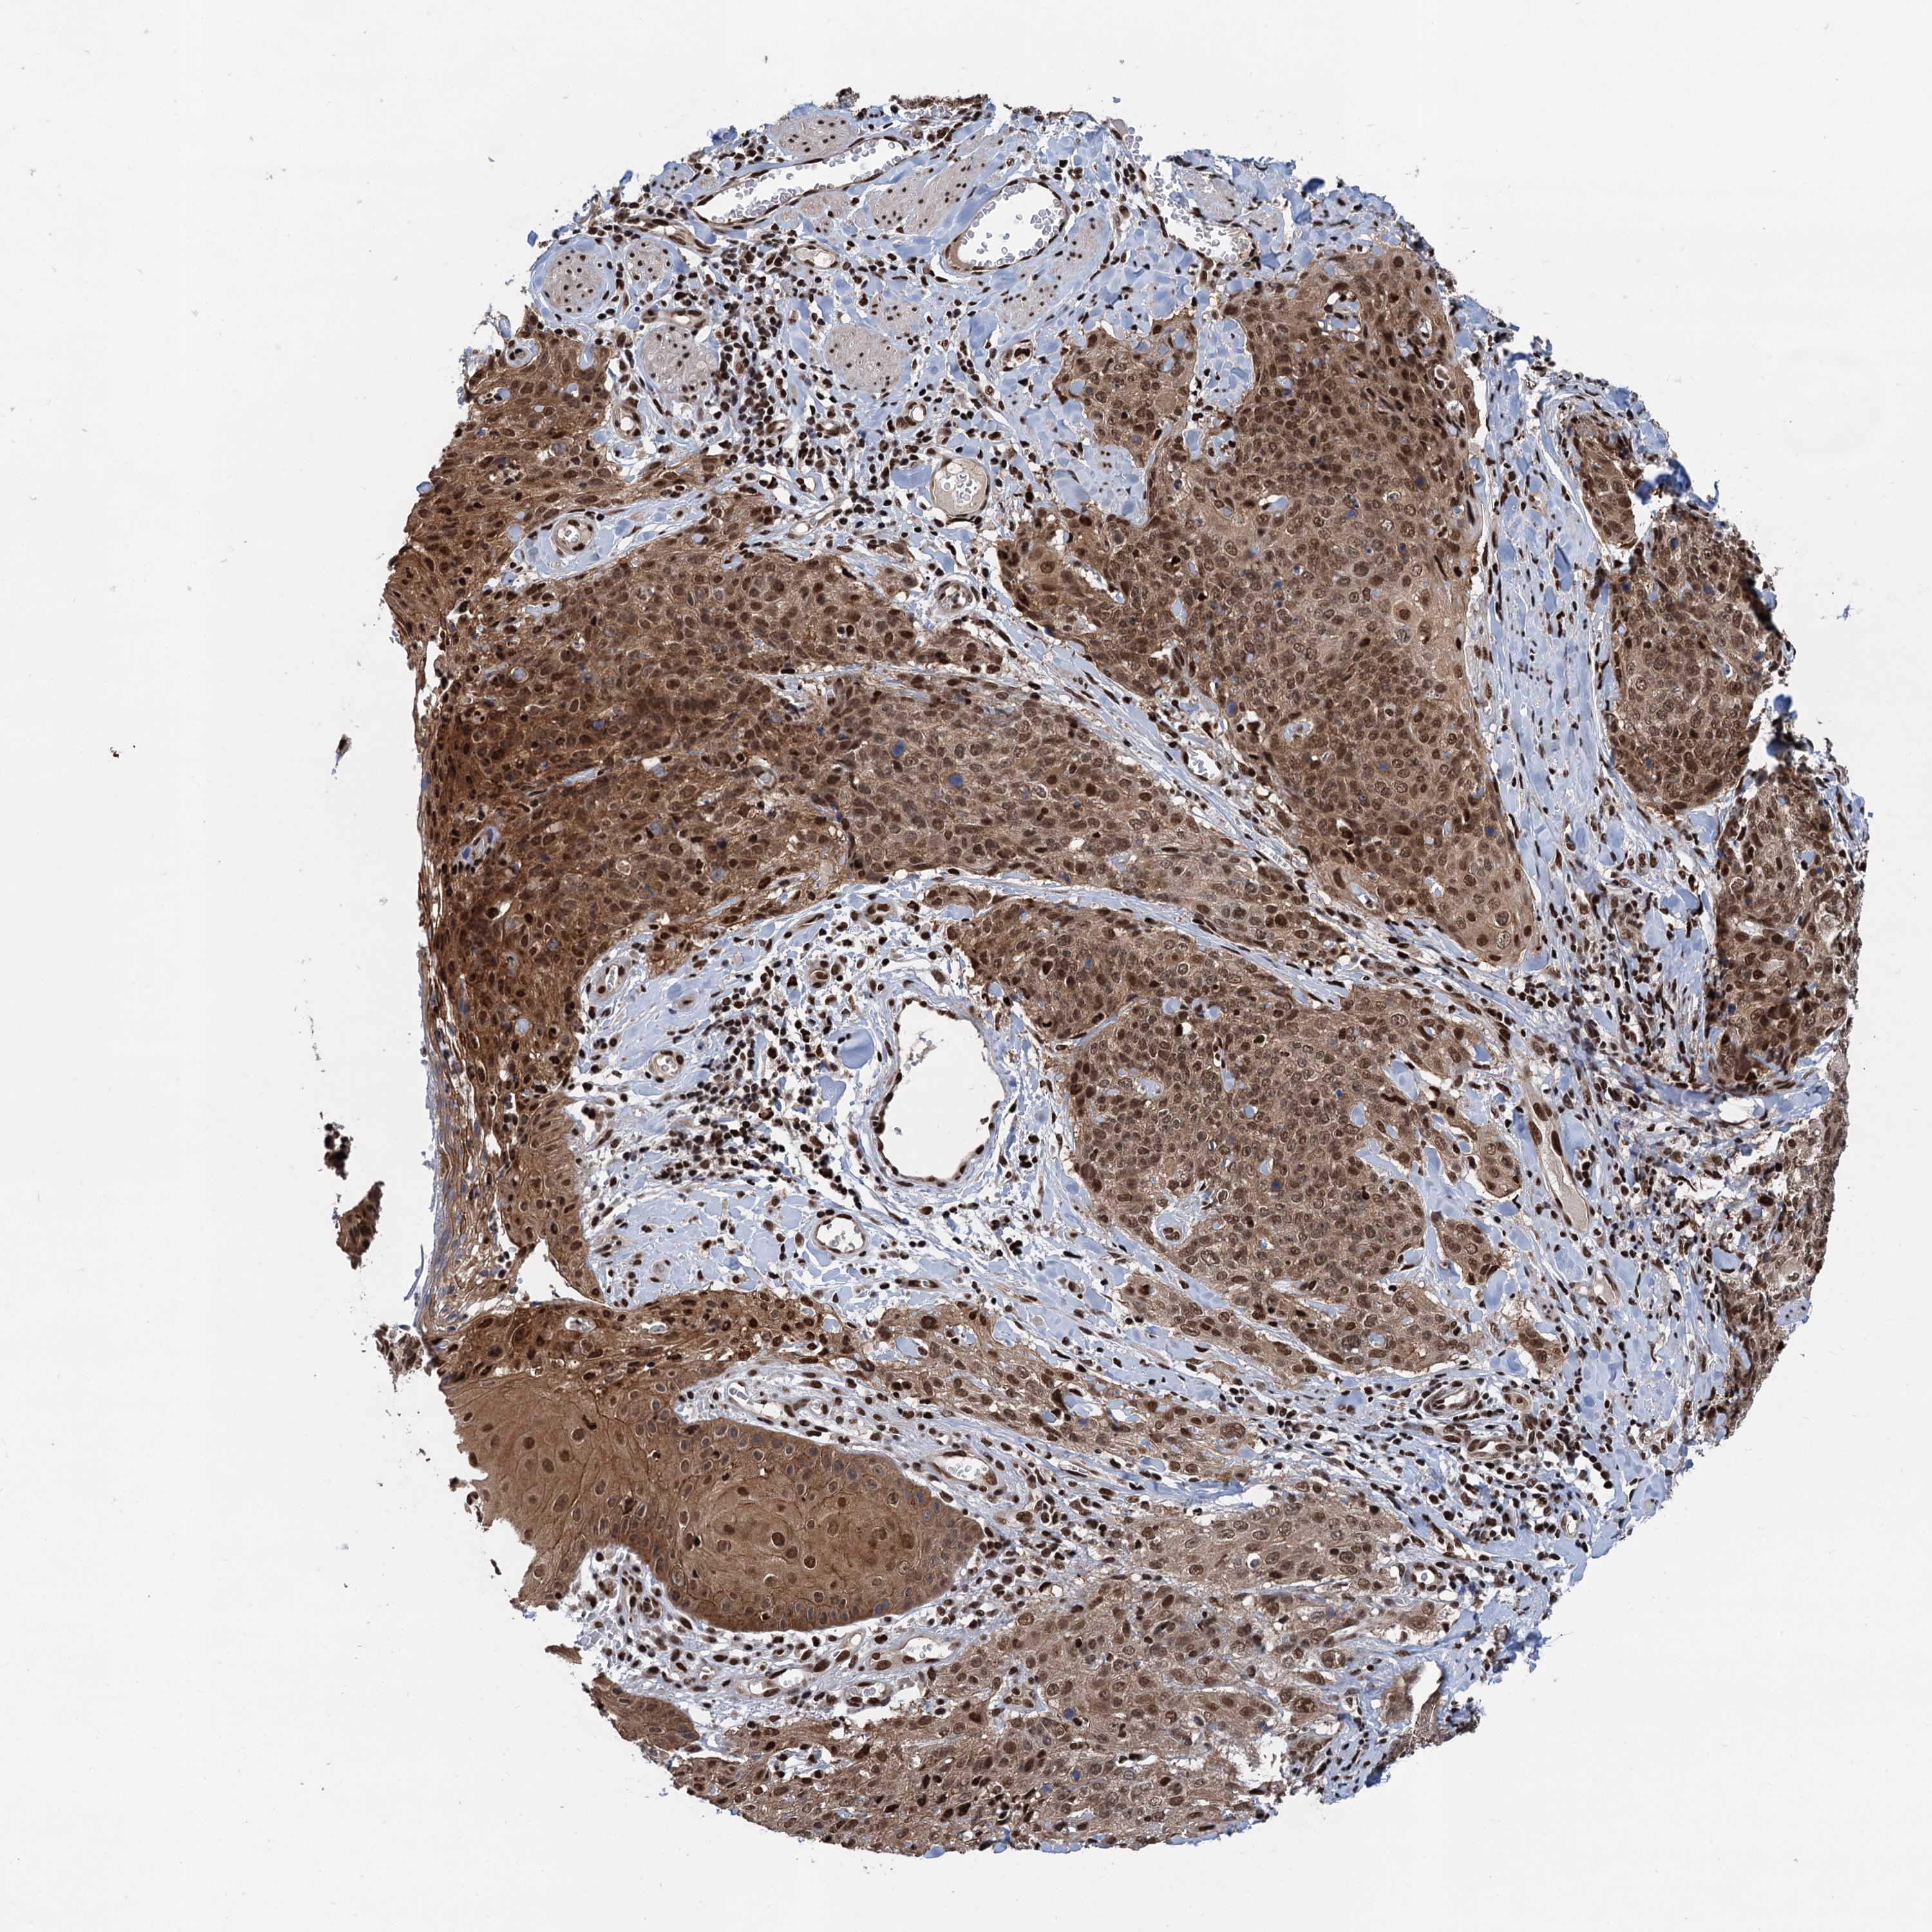

SKIN CANCER - Protein expressioni

A mouse-over function shows sample information and annotation data. Click on an image to view it in a full screen mode. Samples can be filtered based on level of antibody staining by selecting one or several of the following categories: high, medium, low and not detected. The assay and annotation is described here.

Each image is clickable and will lead to virtual microscopy that enables deeper exploration of all samples and also displays staining intensity scores, fraction scores and subcellular localization as well as patient and tissue information for each sample.

Antibody HPA040905

Staining

High

Intensity

Strong

Quantity

>75%

Location

Nuclear

Cytoplasmic/membranous

Cytoplasmic/membranous,nuclear

Basal cell carcinoma